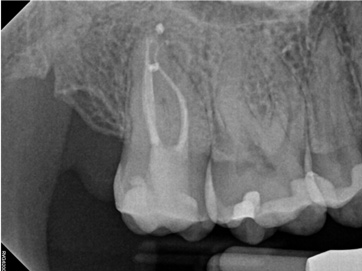

As indicated in Figure 11, the mesial aspect of the distal canal was never touched by instruments, yet he was able to clean, evidenced by the postoperative image. In the past, a case with this level of difficulty would have required at least two appointments, with an interim medication of calcium hydroxide, but the case was treated in a single-visit appointment.  As observed 7 months later (Figure 12), the patient returned completely asymptomatic, and complete bone healing had occurred that exceeded initial expectations.

Fig 11. Case 2: Significant bone loss on the mesial and apical aspect suggested a potential vertical fracture (Fig 9 and Fig 10). Radiographic images were taken immediately postoperatively (Fig 11) and 7 months postoperatively (Fig 12).

Figure 11

Fig 12. Case 2: Significant bone loss on the mesial and apical aspect suggested a potential vertical fracture (Fig 9 and Fig 10). Radiographic images were taken immediately postoperatively (Fig 11) and 7 months postoperatively (Fig 12).

Figure 12